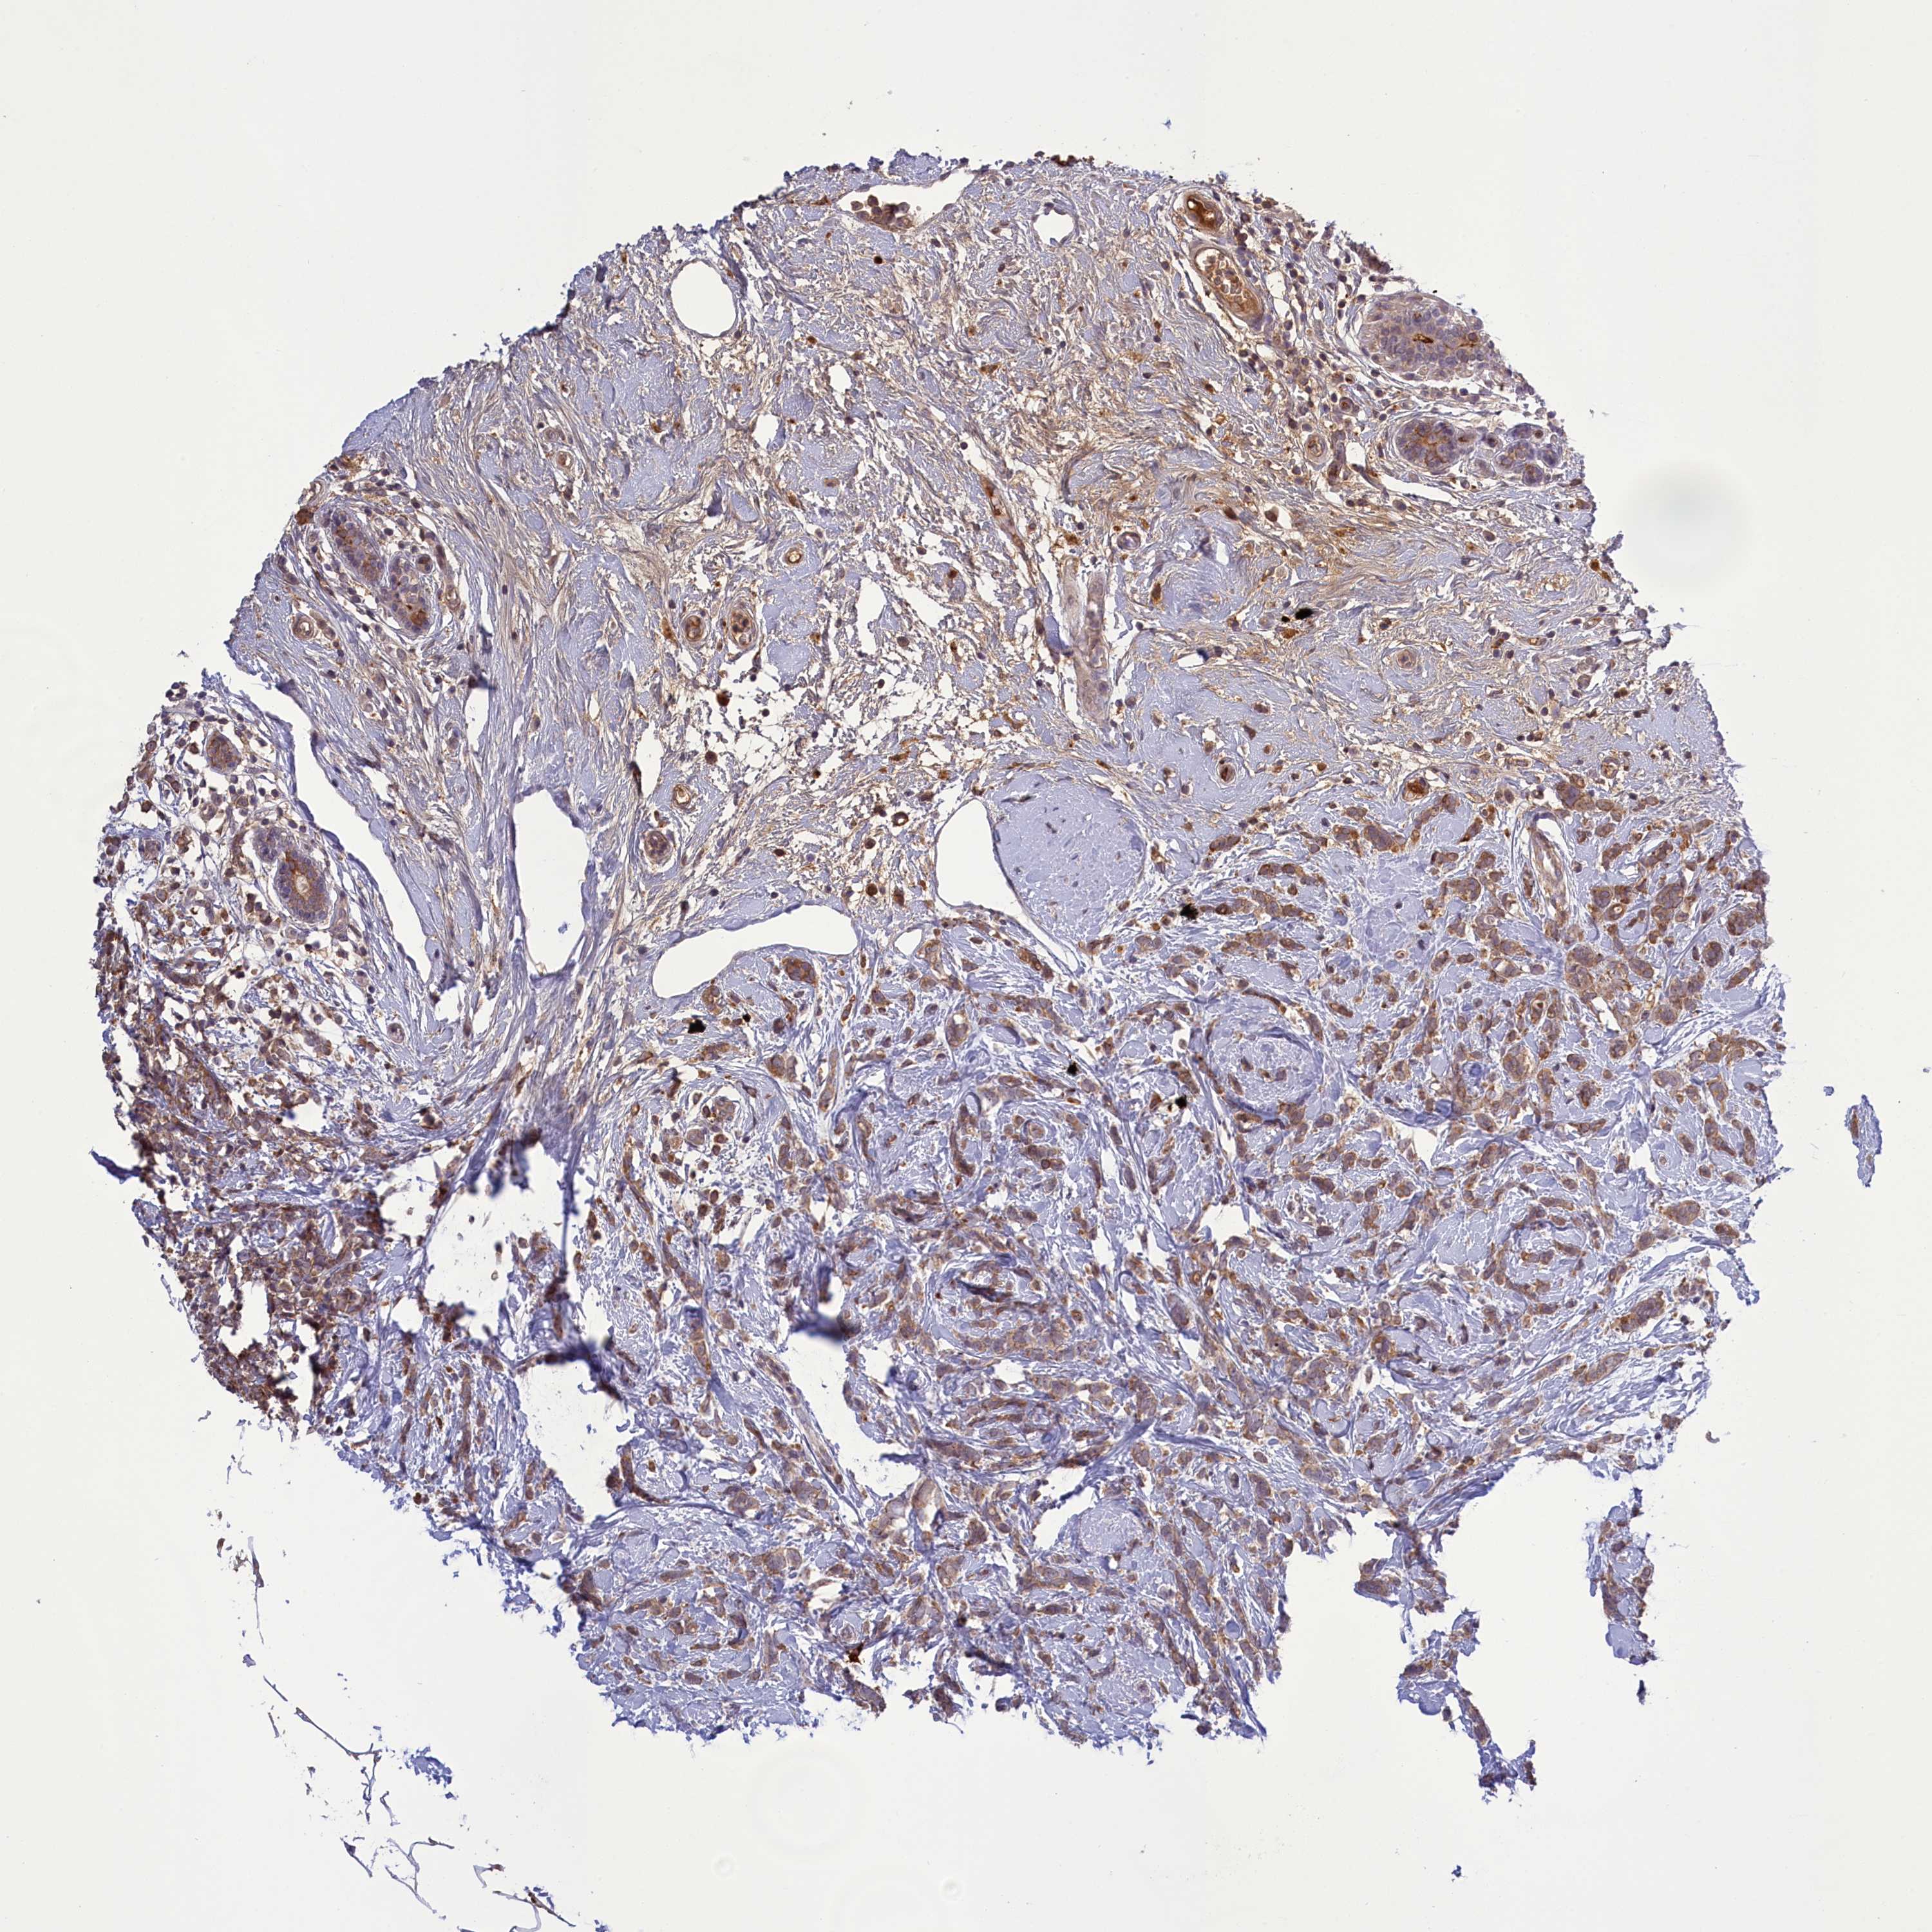

CANCER BREAST CANCER Show tissue menu

BRCA TCGA BRCA VALIDATION PROTEIN EXPRESSION

Breast cancer

Human cancer

Average pTPM 2.6

Number of samples 1022